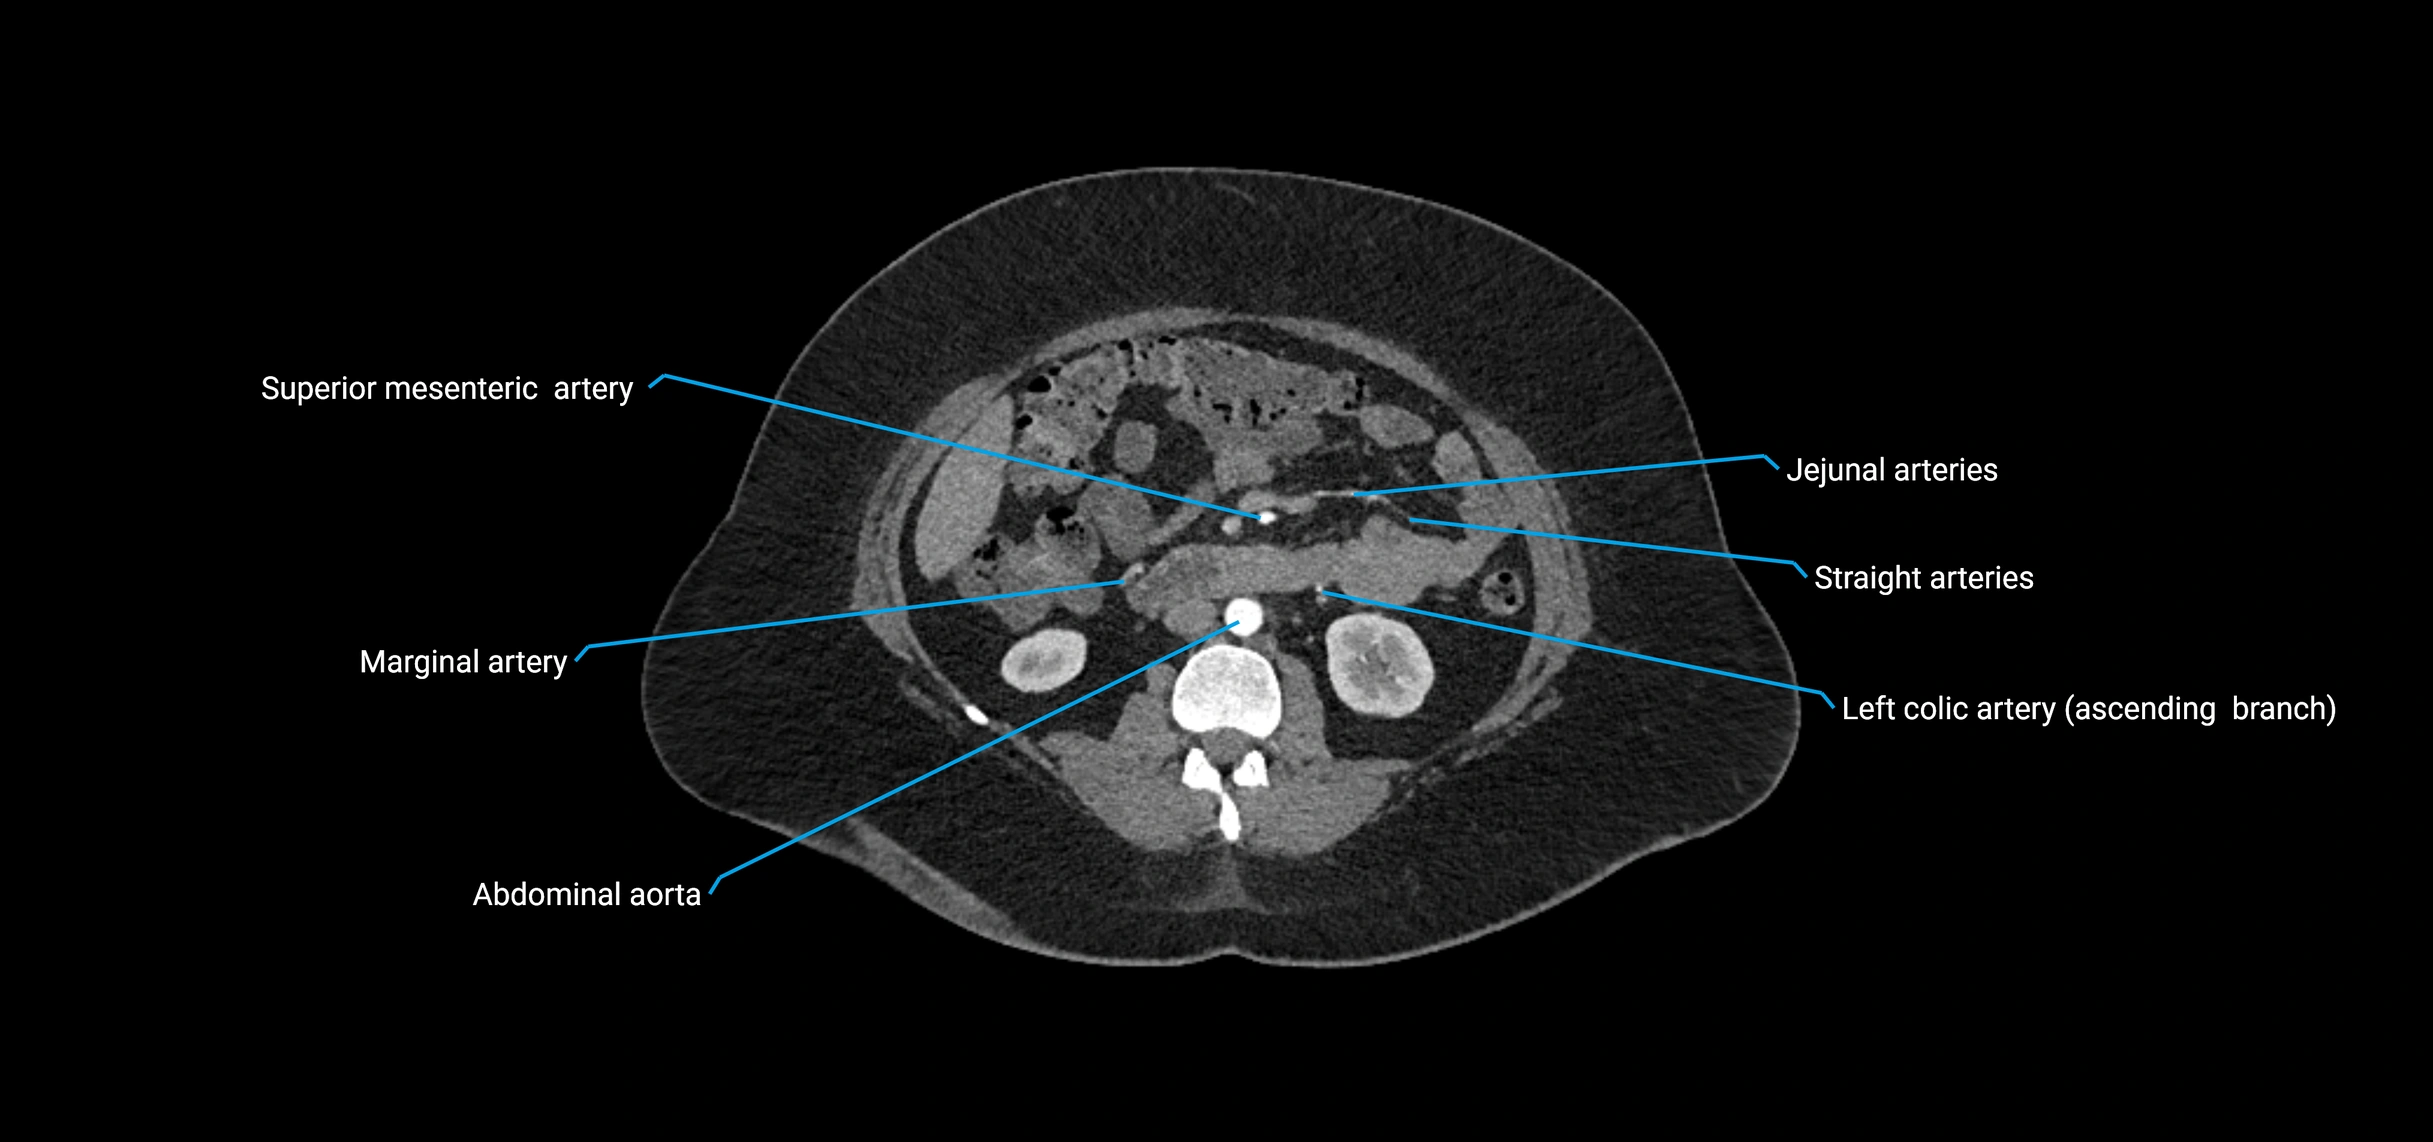

Contrast-enhanced CT (CTA):

• Gold standard for abdominal aortic imaging

• Provides excellent detail of lumen, wall, aneurysm, thrombus, and branch vessels

• Multiplanar and 3D reconstructions help in aneurysm measurement, stent graft planning, and dissection evaluation

• Detects acute rupture, traumatic injury, or occlusion with high sensitivity